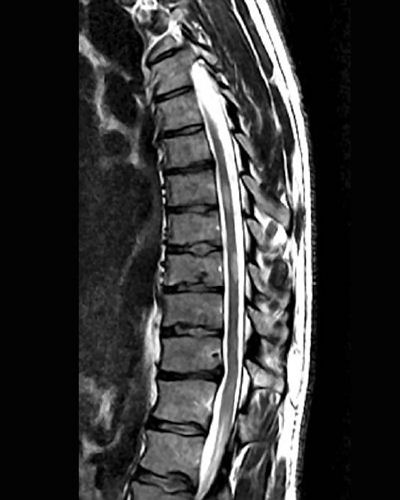

T2 image of spinal cord